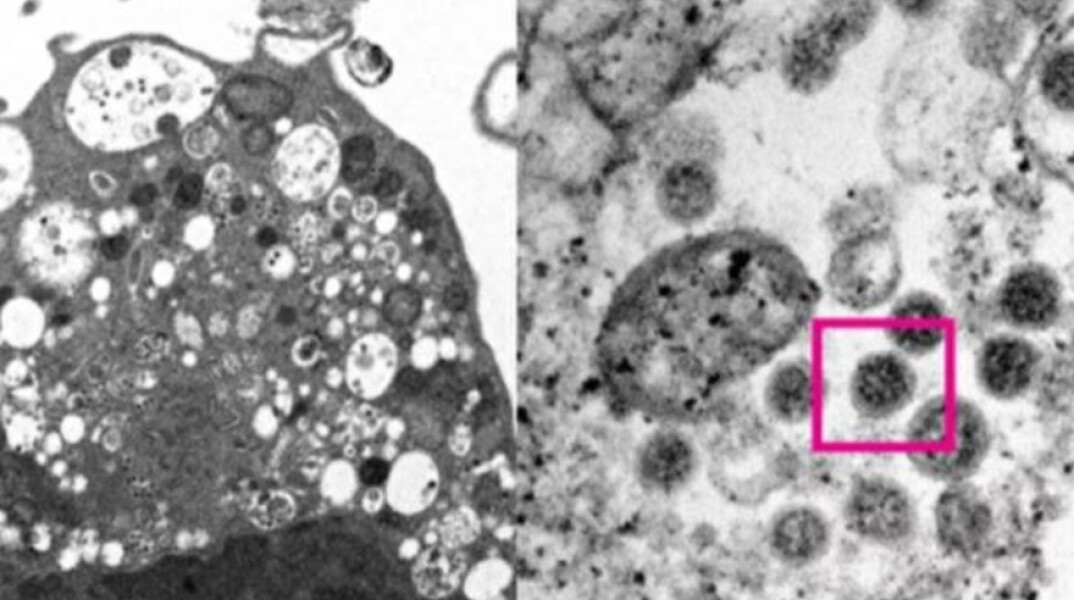

Την πρώτη φωτογραφία που απεικονίζει την παραλλαγή Όμικρον κάτω από το ηλεκτρονικό μικροσκόπιο, δημοσιοποίησε το Πανεπιστήμιο του Χονγκ Κονγκ.

Ειδικότερα, οι επιστήμονες κατάφεραν να λάβουν μια ηλεκτρονική μικρογραφία από κύτταρο του νεφρού ενός πιθήκου που είχε μολυνθεί από την Όμικρον και παρουσίασαν πώς μοιάζει.